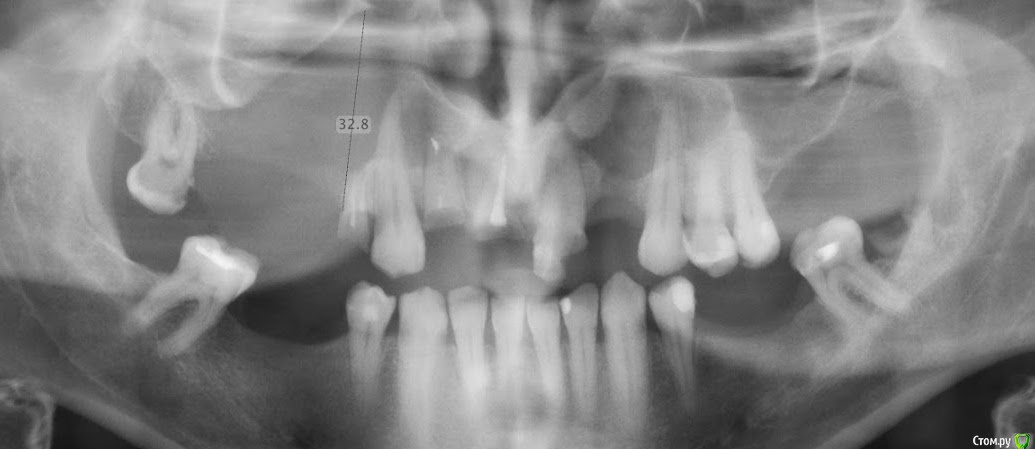

ZeNiT Опубликовано 30 декабря, 2018 Поделиться Опубликовано 30 декабря, 2018 Привет! Коллеги помогите с составлением плана лечения. Опыта с удалением таких кист нет. В будущем планируется имплантация. http://i.piccy.info/i9/42d81e6d0688034efe9a76e910cb2919/1546161955/216971/1291971/k_1110_sta.jpghttp://i.piccy.info/a3/2018-12-30-09-25/i9-12869509/551x551-r/i.gif http://i.piccy.info/i9/6b808c1dc825cf38577d9661f0199b36/1546161979/189129/1291971/k_1110_sta_2.jpghttp://i.piccy.info/a3/2018-12-30-09-26/i9-12869510/551x551-r/i.gif Ссылка на комментарий

Dr.Dzygar.A Опубликовано 13 декабря, 2019 Поделиться Опубликовано 13 декабря, 2019 Привет! Коллеги помогите с составлением плана лечения. Опыта с удалением таких кист нет. В будущем планируется имплантация.Существует методика марсупиализации, заключается в снятии внутреннего давления кисты путём дренажа . После некоторого времени и уменьшения образования в размерах , производится классическое удаление ЛОРом или по Колдуэллу-Люку http://i.piccy.info/i9/42d81e6d0688034efe9a76e910cb2919/1546161955/216971/1291971/k_1110_sta.jpghttp://i.piccy.info/a3/2018-12-30-09-25/i9-12869509/551x551-r/i.gif http://i.piccy.info/i9/6b808c1dc825cf38577d9661f0199b36/1546161979/189129/1291971/k_1110_sta_2.jpghttp://i.piccy.info/a3/2018-12-30-09-26/i9-12869510/551x551-r/i.gif Ссылка на комментарий